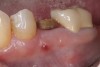

Fig 22. Bone graft was placed in the socket and a d-PTFE barrier was used to cover the graft. The bone graft material was placed beyond the alveolar housing to accommodate shrinkage of graft material and to facilitate attaining a wide alveolar ridge. The barrier was removed after 5 weeks.

Figure 22

Fig 23. Implant inserted in a regenerated ridge after 6 months healing.

Figure 23